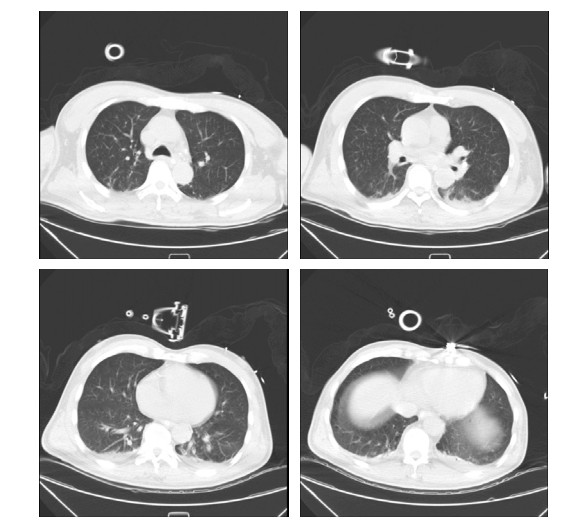

1 资料与方法患者男性,58岁,因“头晕、黑矇3 d,意识不清15 h”于2021-07-07 18:53急诊以“意识障碍待查”收入本院重症医学科。患者3 d前无明显诱因出现头晕、黑矇,共发作7~8次,每次持续5~10 min后自行缓解,上述症状与体位无关,不伴有头痛、耳鸣、视物双影及视物旋转,无发热,曾于当地医院就诊考虑“眩晕症”,给予静点川芎嗪及血栓通后上述症状有所缓解。于入本院前15 h如厕时被家属发现倒地,呼之不应,无抽搐发作,无尿便失禁,无舌咬伤及呕吐,急由120救护车送至当地医院,测体温42.0℃(距离发病1 h),行头部及肺部CT未见明显异常,肝肾功能及降钙素原结果均正常,为求明确诊疗转诊至本院,急诊以“意识障碍待查”收入重症医学科。病程中无咳嗽、咳痰,无尿急、尿频、尿痛,无恶心、呕吐,无腹痛、腹泻。既往史情况:发现高血压病史1年,血压最高160/80 mmHg(1 mmHg=0.133 kPa),未系统诊治及监测。脑梗死病史1年。吸烟史20年,约10支/d,未戒。饮酒史20年,约100 g/d,戒酒1年余。入科查体:体温39.1℃,脉搏114次/min,呼吸23次/min,血压129/80 mmHg,外周血氧饱和度98%(鼻导管吸氧,氧流量3 L/min)。意识不清,GCS评分5分,双侧瞳孔等大同圆,直径约4.5 mm,直接、间接对光反射迟钝,皮肤、巩膜无黄染,咽部无红肿,扁桃体无肿大,气管居中,听诊双肺呼吸音清,未闻及干湿啰音。心率114次/min,律整,各瓣膜听诊区未闻及杂音及额外心音。腹软,肝脾肋下未触及,肠鸣音3~4次/min。双下肢无水肿,项强征阴性,双侧babinski征阳性,kernig征阴性,余查体不配合。辅助检查(2021-07-07,当地医院),血常规:WBC 12.3 × 109/L, NE% 67.6%,PLT 245 × 109/L,PCT 0.18 ng/mL, 肌酸激酶420 U/L,感染标志物:乙肝(−),丙肝(−),肝功能:AST 50 U/L,ALT 40 U/L, 入科诊断:意识障碍待查、发热原因待查。入科后给予降温、促醒对症治疗,约6 h后体温降至38.5℃,但患者意识无恢复,无自主咳痰能力,双肺可闻及痰鸣音,于2021-07-08给予气管插管及呼吸机辅助通气,同日出现血压下降,给予补液、升压(去甲肾上腺素)对症治疗。入科后进一步完善相关检查包括,出血热抗体:阴性,呼吸道病原核酸检测:阴性,IL-4 4.05 pg/mL,IL-6 229 pg/mL,IL-10 22.90 pg/mL,肌酸激酶13 383 Μ/L,肌红蛋白4 077 ng/mL;血栓弹力图:R 10.8 min,MA-CK 21.4 mm,K 23.4 min,综合凝血指数-19.9;肝功能:AST 2 643.0 M/L,ALT 2 711.9 M/L,ALB 32.1 g/L,TB 142.5 μmmol/L,DB 85.1 μmmol/L,CB 57.4 μmmol/L;肾功能:Scr 94.3 μmol/L、BMN 7.1 mmol/L;血常规及凝血相关指标变化见表 1;头部CT提示双侧小脑半球、脑干、双侧枕叶、丘脑、放射冠、半卵圆中心低密度影(图 1);肺部CT提示支气管炎、双肺散在炎症、胸主动脉及冠脉动脉硬化(图 2)。综合病史、体征和辅助检查明确临床诊断为:椎基底动脉脑梗死、中枢性高热、多器官功能障碍综合征(循环、肝脏、血液)、横纹肌溶解综合征,给予脱水降颅压、营养神经、促醒、纠正凝血异常对症治疗,患者病情无好转,于2021-07-09家属放弃治疗,出院后死亡。

| 图 2 2021-07-09患者肺部CT |